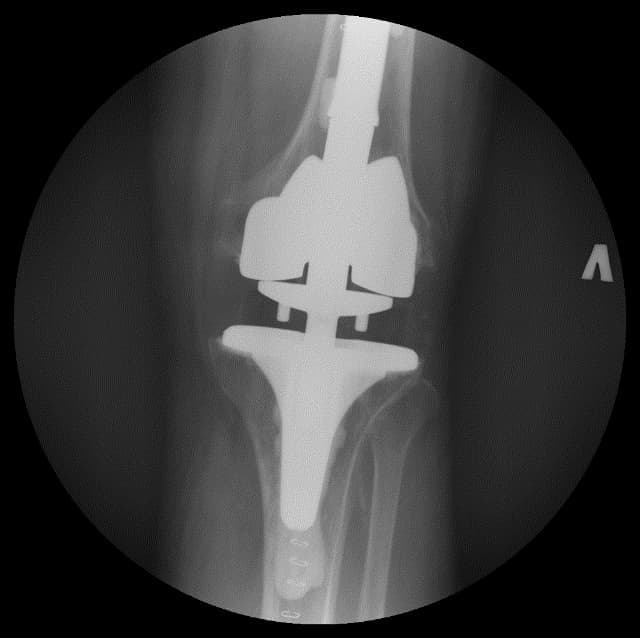

Үе дайрсан ясны анхдагч хавдар, ясны дутмагшлын үед хийгдэх мэс засалimg15Үе дайрсан ясны анхдагч хавдар, ясны дутмагшлын үед хийгдэх мэс засалimg16

Зураг 3. Мэс заслын дараах рентген зураг. Эгц урд, хажуугаас авсан байдал